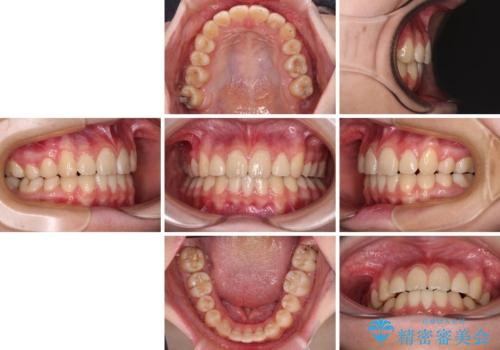

目立つ八重歯を治したい インビザラインによる矯正治療

まずは補助装置を用いて八重歯を改善し、インビザラインにて歯列を整えましたが、当初の懸念が的中し、臼歯部の咬合を安定させることができませんでした。

海外留学の予定もあったため、後半は上下ワイヤー装置にて矯正治療を継続し、違和感なく咬合させることとなりました。